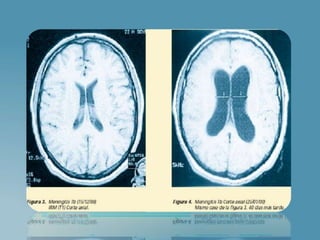

RICH – MCCORDOCK: (Desarrollo 2 etapas):

1) Diseminación a partir de pulmón con formación de

tuberculomas en la corteza.

2) Ruptura de tuberculomas liberando bacilos al LCR

“ Meningitis Tuberculosa”.

 Exudado inflamatorio meningeo

 Vasculitis de arterial

 Trastornos en el flujo de LCR

(Exudado bloquea las cisternas de la fosa

interpeduncular y ocasiones Luschka y Magendie)

PRODUCIENDO HIDROCEFALEA

BASE SEL CEREBRO

CISTERNAS LLENAS

DE EXUDADO

GELATINOSO

INFLAMACION:

FIBRINA

LINFOCITOS

HISTIOCITOS

CEL PLASMATICAS

INFLAMACION EN

LOS PLEXOS

COROIDES

DILATACION

VENTRICULAR